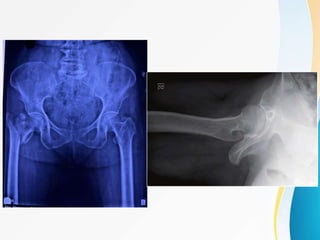

RADIOGRAPHIC IMAGING :

• Anteroposterior view - to know fracture

obliquity , quality of the bone .

• cross table lateral view - to assess size,

location and comminution of posterior fracture

fragment and helps to determine the fracture

stability .

• CT and MRI

• Technetium bone scan - suspected hip fracture

but not apparent to standard radiographs , it

requires 2-3 days to become positive .

RADIOGRAPHIC IMAGING : •Anteroposterior view - to know fracture obliquity , quality of the bone . • cross table lateral view - to assess size, location and comminution of posterior fracture fragment and helps to determine the fracture stability . • CT and MRI • Technetium bone scan - suspected hip fracture but not apparent to standard radiographs , it requires 2-3 days to become positive .